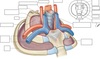

Label the diagram

Label this diagram

Label the diagram

What vessels go to and from the heart inside the thoracic inlet?

- Internal jugular vein

- Subclavian veins

- Subclavian arteries (posterior to the above)

- Common carotid arteries (posterior to the above )

Label this diagram